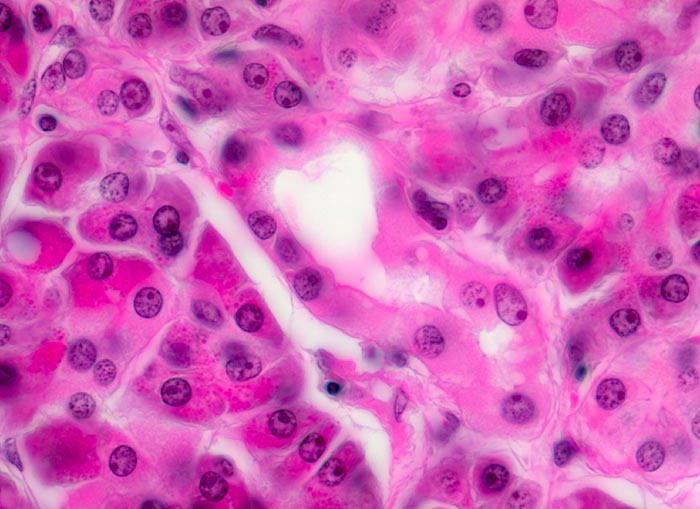

Morphologische Merkmale:

• Unregelmässige Anordnung der Drüsen (keine Läppchenarchitektur erkennbar).

• Kribriforme Drüsenformationen.

• Inkomplette Drüsen mit unvollständigen Lumina und Infiltration des Stromas durch Tumoreinzelzellen.

• Nekrotische Tumorzellen in den Drüsenlumina.

• Ausgeprägte Polymorphie und Hyperchromasie der Tumorzellkerne.

• Desmoplastisches Stroma.